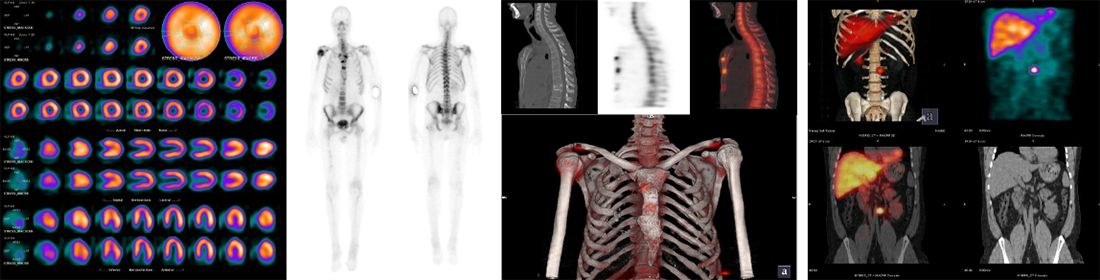

PET-CT

PETとは、Positron Emission Tomography(陽電子放出断層撮影)の略で、放射能を含む薬剤(放射性医薬品)を用いる核医学検査です。この薬剤を注射して体内における薬剤の分布を専用装置で撮像することにより、全身のがん検索や脳の状態を調べることができます。

アルツハイマー病の最新治療薬であるレカネマブの使用適正があるのかを調べる「アミロイドPET検査」が近日中に検査可能となる予定です。

- 悪性腫瘍(早期胃がんを除く)・てんかん

- 虚血性心疾患における心不全・心サルコイドーシス

- Cartesion Prime Luminous Edition

SPECT-CT(RI検査)

SPECT-CTとはSingle Photon Emission Computed Tomography(単一光子放射断層撮影)の略で、放射性医薬品を体内に注射し、その薬剤の集積・分布を、特殊な装置を用いて放射線を検出し、画像化する核医学検査です。

この検査を行うことで様々な臓器の代謝や血流などの機能的な情報を得ることができ、病気の有無や病態の診断に役立ちます。当院のSPECT装置はCT(吸収補正用)装置を搭載しており、従来機より病変抽出率が向上しています。

脳領域

- 脳血管障害による脳梗塞、一過性脳虚血発作、脳動脈狭窄症などの診断

- アルツハイマー型、レビー小体型、血管性認知症などの認知症診断

- てんかんによる焦点部位の血流異常検出

- 狭心症、心筋梗塞などの虚血性心疾患の血流評価

- 心不全・心筋症に対する心筋機能や交感神経機能評価

- 心筋梗塞後の生存心筋評価

- がんの骨転移などの骨転移検索

- 疲労骨折や微小骨折の診断

- 炎症・感染症:骨髄炎、膿瘍などの評価

- 腎動態評価(レノグラム):腎機能障害、閉塞性尿路疾患、腎血管性高血圧症の診断

- NM CT850